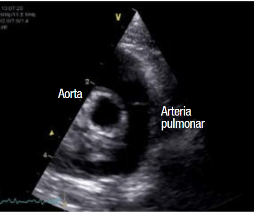

2. Ecocardiografía

Técnica ecocardiográfica

Ecografía del corazón sano

Ecografía de las alteraciones cardiacas